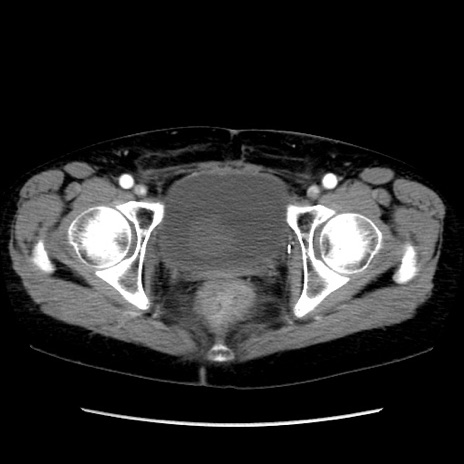

症例32(横断像)

【症例】40歳代 女性

【主訴】上腹部痛、嘔気・嘔吐

【現病歴】約9時間前頃から急に上腹部痛、嘔気、嘔吐が出現。改善しないため救急要請。

【既往歴】子宮頚癌(広汎子宮全摘術、放射線療法)、腸閉塞